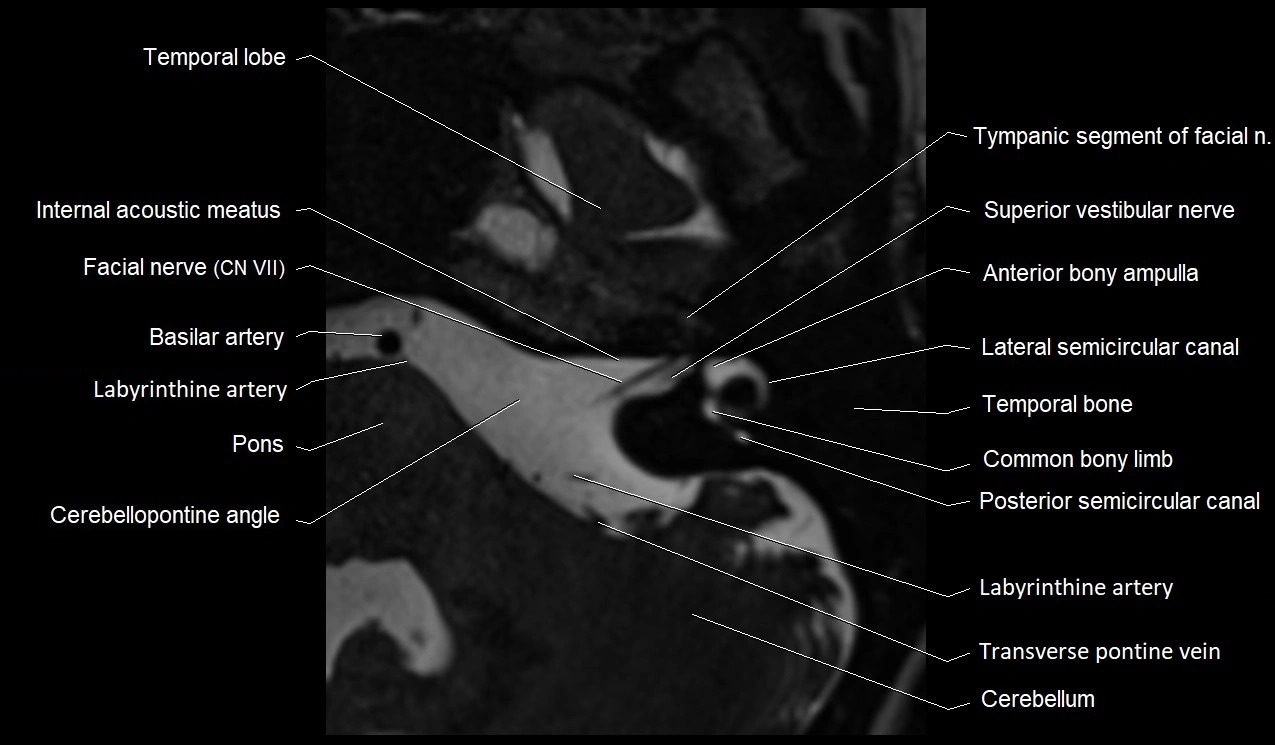

MRI images

image